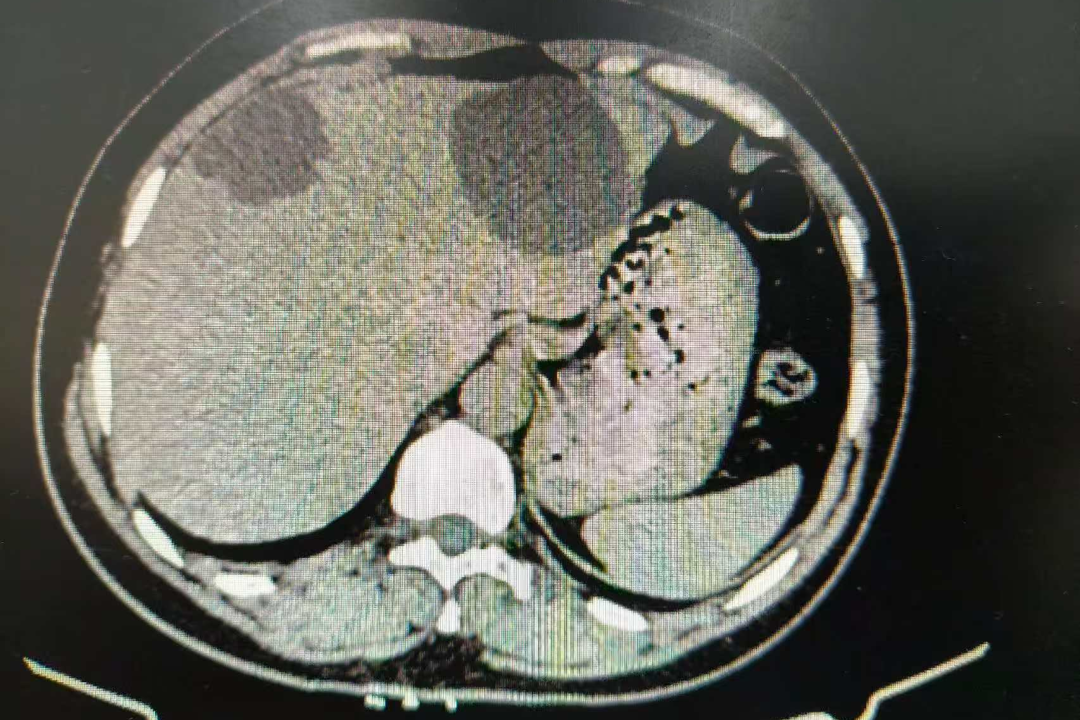

近日,55岁的江阿姨(化名)因“发现肝囊肿4年余”来我院就诊。4年前,她在体检时发现肝囊肿,当时囊肿较小,一直采取保守治疗,每年定期复查肝胆彩超。最近,她常感到上腹隐隐作痛,并伴有饭后饱胀感。复查上腹CT提示,肝囊肿已增大至6.5cm×5.5cm。外院医生建议进行手术开窗引流治疗。江阿姨听说要手术,非常焦虑,担心创伤太大。后来她了解到,我院刘志龙教授可以实施超声引导下的肝囊肿硬化治疗,无需开刀,只需借助一个“小针眼”就能解决囊肿,于是前来我院就诊。

手术前,刘志龙教授通过详细问诊、全面体格检查及辅助检查结果分析,对患者病情做出了充分评估。他还亲自操作肝脏超声,精确评估肝囊肿状况。结果显示,患者肝囊肿直径超过5cm且伴有上腹不适,硬化治疗指征明确。刘教授随后耐心地与患者及家属沟通病情与手术方案,逐一解答疑问,使其紧张情绪得到极大缓解,患者及家属最终欣然同意接受治疗。

术前上腹CT